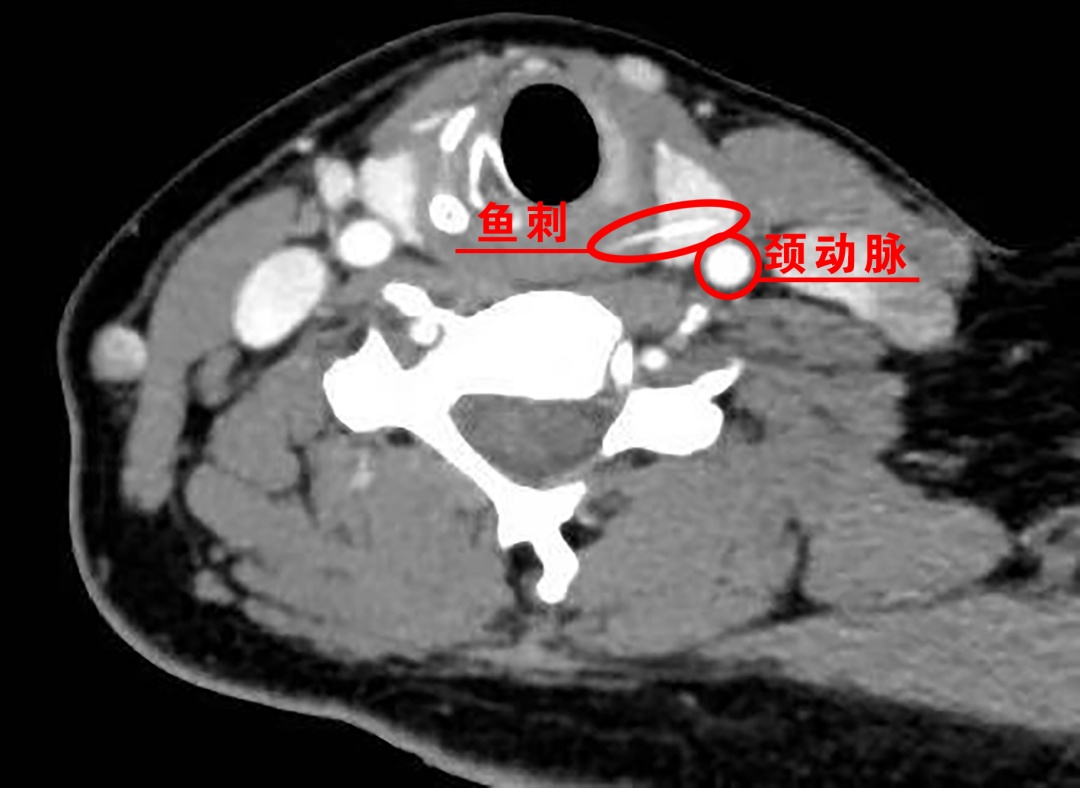

瑞金医院普外科主任医师、瑞金医院南翔分院院长吴庆华告诉记者,由于张女士鱼刺被卡时间较长,医院立即为她做了颈部增强CT检查,结果显示,食管入口偏左侧可见一条约1.7厘米的高密度条状影,已穿破食管扎进了甲状腺组织,鱼刺末端距离左侧甲状腺被膜(紧邻左侧颈总动脉)仅约3.4毫米!

鱼刺扎进甲状腺绝非小事

更因紧邻颈动脉等大血管

随时可能因移位

刺破血管导致瞬间大出血休克;